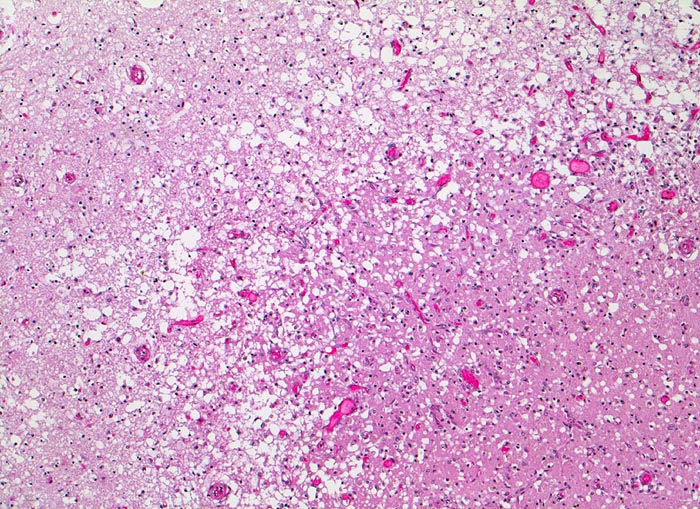

PathoPic – image database / PathoPic ID 3524 - anämischer Hirninfarkt

anämischer Hirninfarkt

vaskulär / Durchblutungsstörung

Hirn parietal

Randbereich des Infarktes mit spongiotischer Auflockerung des Hirnparenchyms, Gefässneubildungen und unscharfer Mark-Rinden Grenze. In der helleren Rinde links im Bild sind keine Neuronen sichtbar.

Vor 7 Tagen Entwicklung eines Hemisyndrom links.